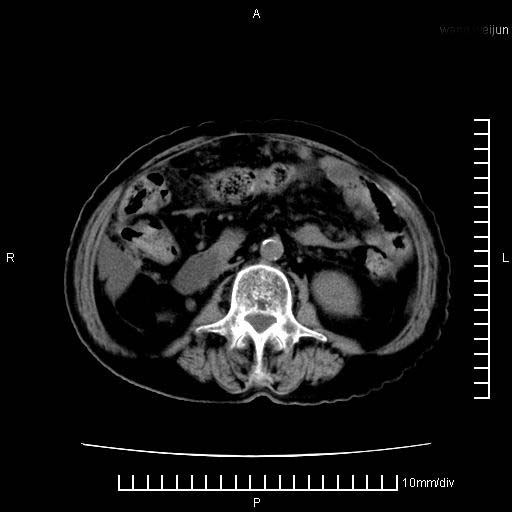

标题: CT28280:腹部增强:女性,80岁

上腹疼痛月余,外院核磁诊断胰腺癌。现临床示右下腹可明显触及包块,可片子上怎么没有看到?

1.胰腺颈体部癌。

2。腹腔积液。

3。右胸腔积液,伴右肺下叶部分萎陷。

4。右肾盂囊肿。

胰腺体部癌累及周围器官,腹膜、粘连

1。胰腺ca伴腹膜腔转移

2。肝左叶低密度灶,考虑转移可能

胰腺体部癌累及周围器官,腹膜、粘连,临床摸到的可能是粘的组织

胰腺结构模糊,胰尾部见囊性包块,周围脂肪密度增高,左肾前筋膜增厚,胸水、腹水。不符合胰腺ca伴腹膜腔转移。考虑胰腺炎伴假性囊肿形成、胸腹腔积液。

右肾盂囊肿。